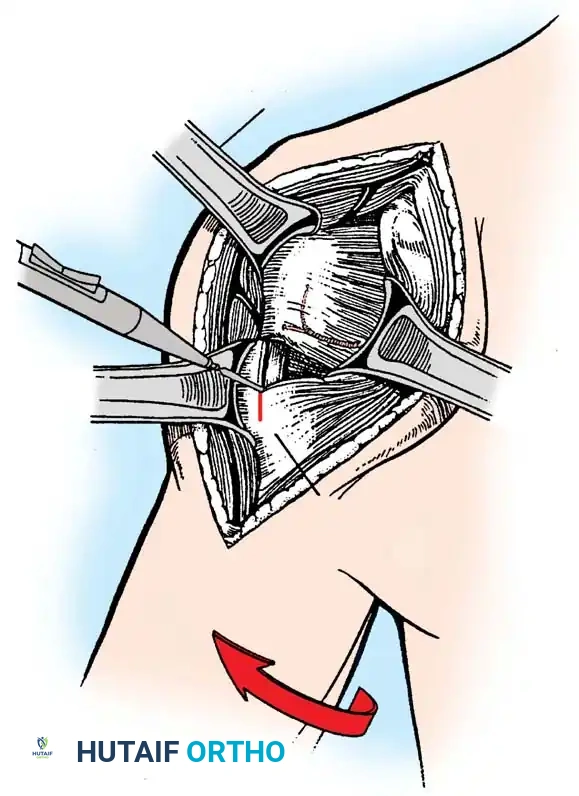

2. Subscapularis Management

The subscapularis is the gatekeeper to the joint. It can be managed via a tenotomy (1 cm medial to the lesser tuberosity), a lesser tuberosity osteotomy (LTO), or a subscapularis peel. LTO provides superior bone-to-bone healing and is increasingly favored.

3. Humeral Head Resection

Dislocate the humeral head anteriorly through external rotation and extension. Remove peripheral osteophytes to identify the true anatomical neck. The humeral cut is made along the anatomical neck, typically at 30 degrees of retroversion and 45 degrees of inclination.

1. Positioning and Approach

The patient is placed in the lateral decubitus position with the arm draped over a bolster. A universal posterior approach is utilized.

- Ulnar Nerve Management: The ulnar nerve must be identified, mobilized, and protected throughout the procedure. Routine anterior transposition is performed at the conclusion of the case.

- Triceps Management: Several options exist, including a triceps-reflecting approach (Bryan-Morrey), a triceps-splitting approach, or a triceps-sparing approach. The Bryan-Morrey approach involves reflecting the triceps from medial to lateral in continuity with the anconeus and forearm fascia.